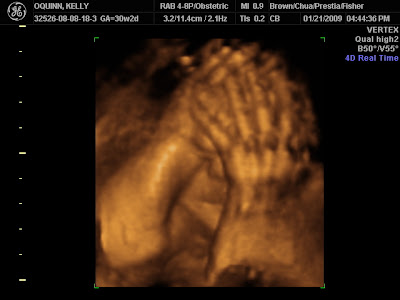

1st Pictures - Minus 2 Months Old!!

Looks like he's camera shy like his mom and dad.

That's Better